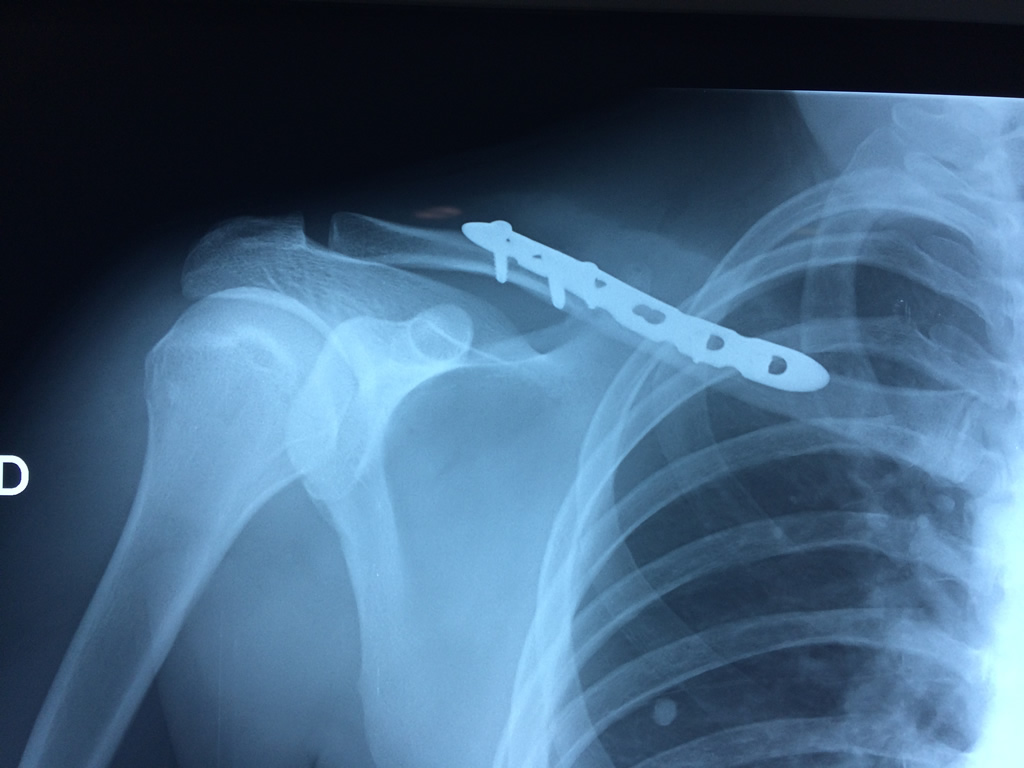

Clavícula

La clavícula es un hueso largo, con forma de "S" itálica, situado en la parte anterosuperior del tórax. Junto con la escápula forman la cintura escapular. Se puede palpar por toda su longitud y se extiende del esternón al acromion de la escápula, siguiendo una dirección oblicua lateral y posterior.

Se considera el único medio de unión entre el miembro superior y el tórax. A pesar de su aspecto, similar al de un hueso largo, posee una estructura semejante a la de un hueso plano, ya que carece de epífisis y de diáfisis, lo que la harían entrar dentro de la clasificación de hueso largo. Carece de un canal medular propiamente dicho.